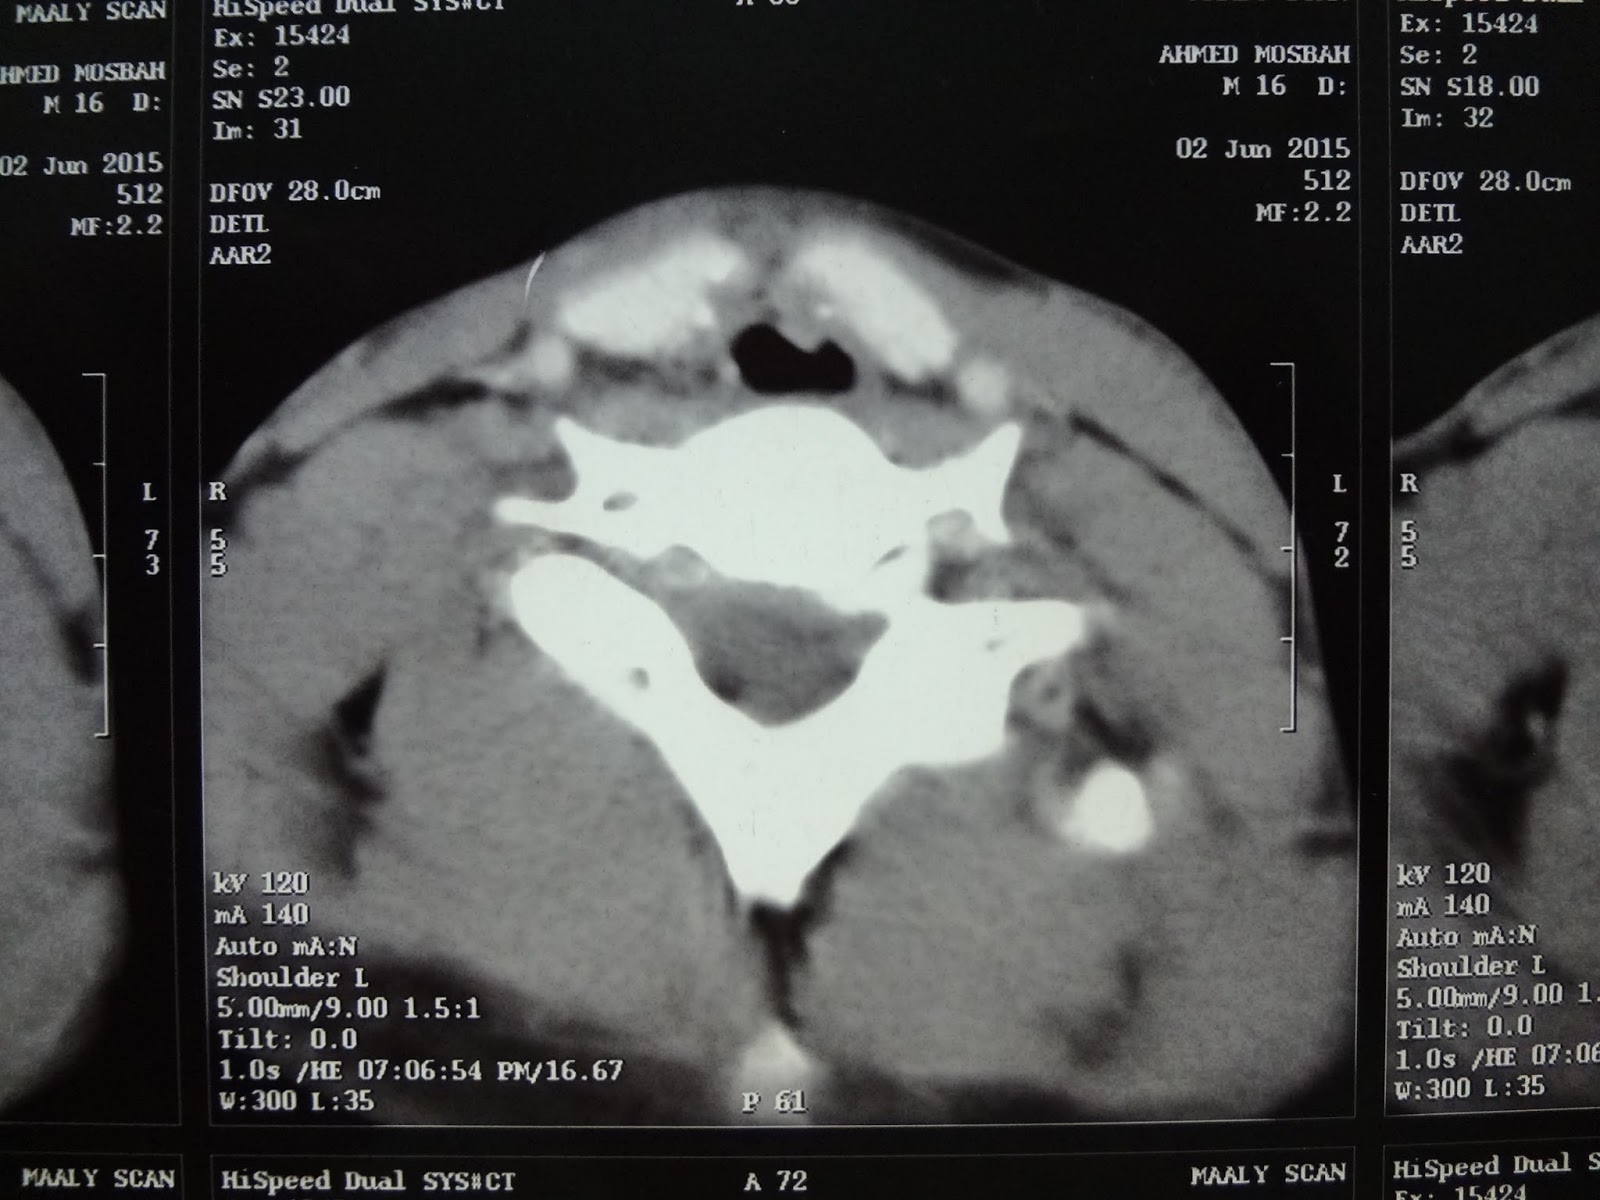

laryngeal tracheal stenosis grade IV . UPPER airway stenosis due to endotracheal intubation. prepared for cricotracheal resection and reanastomosis

Acase of subglottic and upper tracheal stenosis

Grade IV stenosis

Intubated for 18 day from 8 months

Tracheastomized